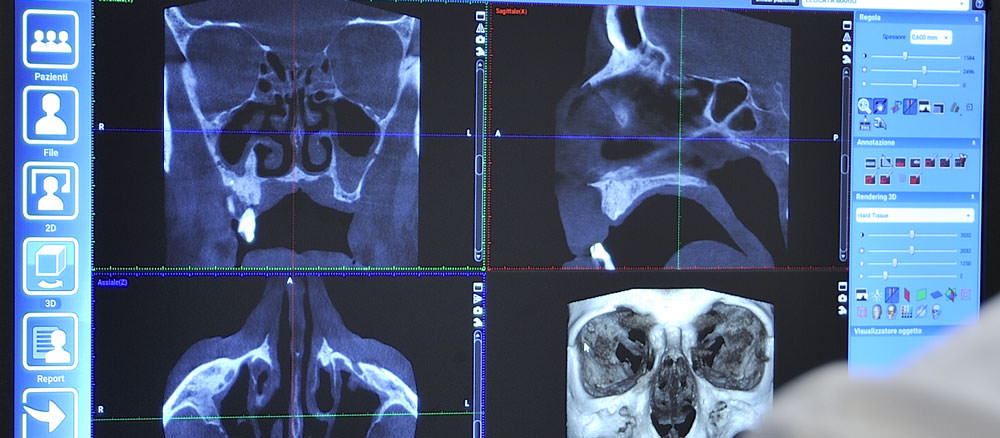

La Radiologia Dentale è un supporto estremamente importante sia per la diagnosi di lesioni clinicamente non manifeste, che per la programmazione ed il controllo dei trattamenti in atto

La sua importanza è andata continuamente aumentando grazie alle apparecchiature all'avanguardia capaci di produrre referti radiografici digitali di altissima qualità.

Presso le Sedi Affidea|CDC si eseguono altri approfondimenti di Radiologia Dentaria come TC Cone Beam e TAC - TC Dentale / Dentascan